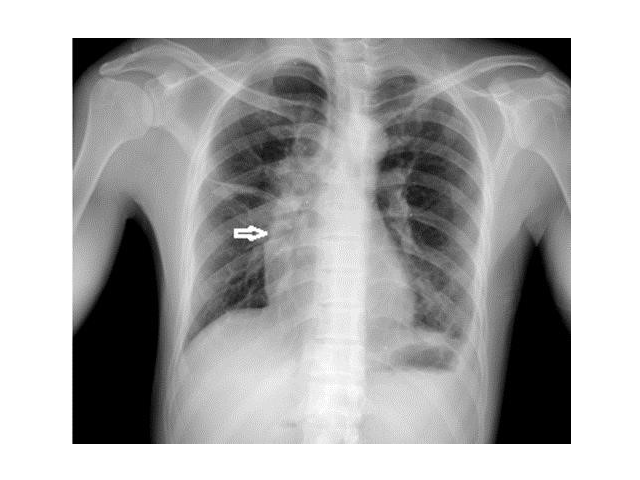

Case Report